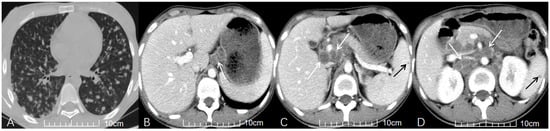

3.3. CT Characteristics of ATBL

4.3. CT Imaging Analysis

4.4. Co-Involvement of Other Sites